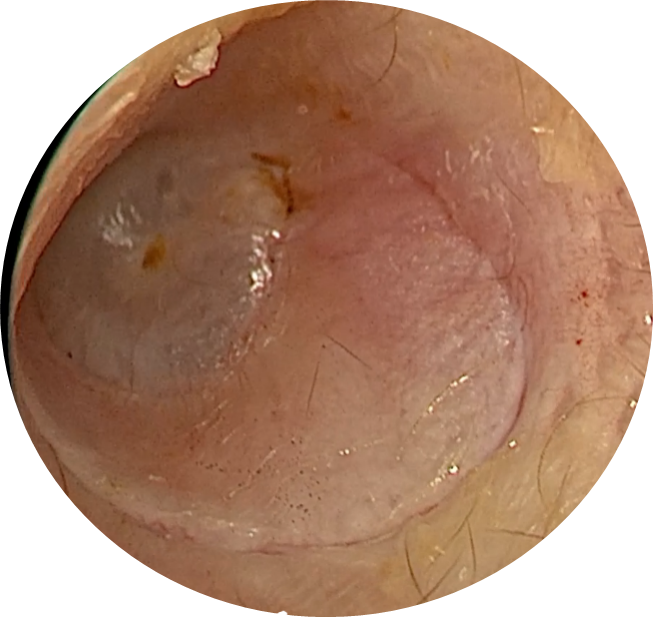

Vue endoscopique de du conduit auditif externe : Incision cutanée